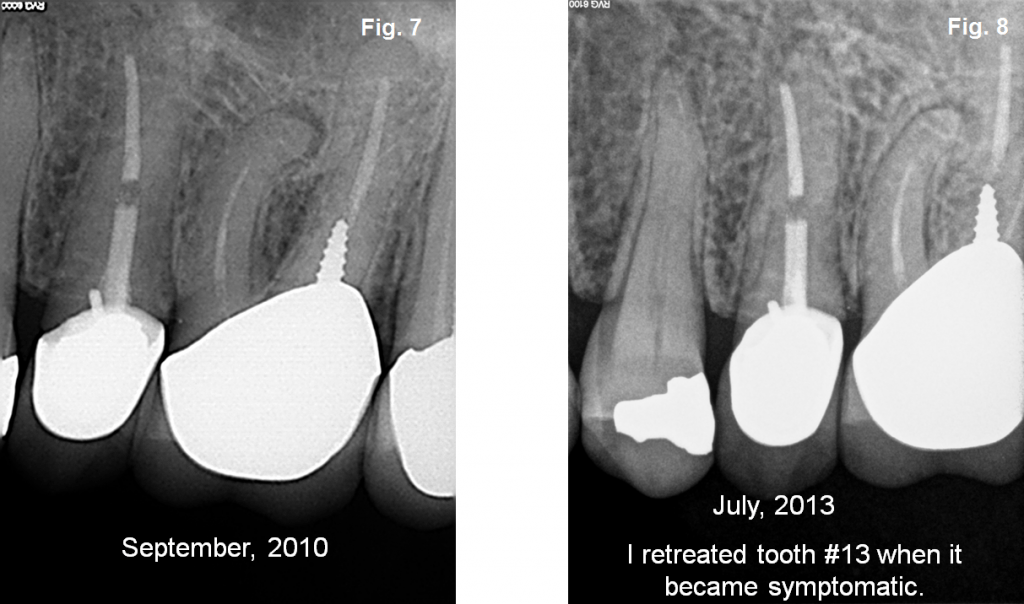

From endo-specialists.com

Endodontic Retreatment Endodontic Specialist of Missouri Endodontics Hershey We are a practice dedicated exclusively to endodontic care. We offer our patients the latest in root canal therapy. Hiltz endodontics in hershey, reviews by real people. Hershey, pa has 68 endodontist results with an average of 23 years of experience and a total of 75 reviews. When the damage goes beyond what can be treated with a filling, we. Endodontics Hershey.